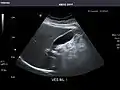

Right kidney

Kidneys: Right and left kidneys measure 11.5 cm and 12 cm in length respectively. No hydronephrosis. Small left lower pole kidney cyst.